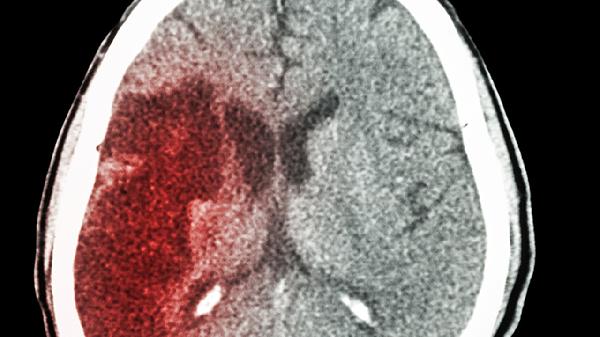

高血压引起的脑梗可通过控制血压、抗血小板治疗、改善脑循环、康复训练、手术治疗等方式治疗。高血压引起的脑梗通常由长期血压控制不佳、动脉粥样硬化、血栓形成、血管痉挛、血液黏稠度增高等原因引起。